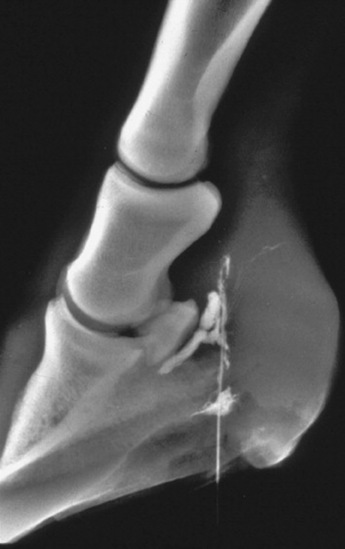

Radiographic examinations should be performed on the affected digits of horses suspected to be developing laminitis. The initial examinations should include lateromedial and 65-degree dorsoproximal-palmarodistal projections. These views should be taken to assess the appearance of the distal phalanx, the soft tissues of the hoof wall and corium, and their relationship. Lateromedial examinations are periodically repeated to check the progression of the disease. Radiographic signs of laminitis include ventral displacement of the extensor process with respect to the coronary groove of the hoof wall, increased distance between the dorsal cortex of the distal phalanx and the surface of the hoof wall, and ventral rotation of the tip of the distal phalanx. Linear radiolucencies are noted interior to the hoof wall in cases where the corium has separated from the epidermal laminae. Increasing degrees of rotation of the distal phalanx and increases in the distance between the dorsal surface of the distal phalanx and the hoof wall indicate progression of the disease (Fig. 38-30).

Fig. 38-30 A, Lateromedial radiograph of a normal digit. Two radiopaque markers can be seen. One has been placed on the block below the foot to mark the bearing surface of the wall, and the other marker identifies the location of the dorsal surface of the hoof wall. Notice that the dorsal surface of the hoof wall and the dorsal cortex of the distal phalanx are parallel, and that the distance between them, the soft tissue thickness (T), is approximately 25% of the distance from the tip of the distal phalanx to the articulation of the distal phalanx and the navicular bone, that is, the length of the distal phalanx (L). B, Lateromedial radiograph of a digit from a horse with severe laminitis. The distal phalanx has dropped ventrally without rotating. This phenomenon is seen in some horses with laminitis. The most consistent radiographic manifestation in such cases is an increased distance between the dorsal cortex of the distal phalanx and the dorsal surface of the hoof wall. The soft tissue thickness, as measured between the dorsal cortex and the dorsal surface of the hoof wall, in this case is 45% the length of the distal phalanx. The soft tissue thickness is normally less than 28% of the distal phalanx length for thoroughbred racehorses. C, Lateromedial radiograph of a digit from a horse with severe laminitis. Note the linear radiolucency dorsal to the distal phalanx (arrowhead). This lucency indicates a separation between the corium and primary epidermal laminae and marks the inner aspect of the hoof wall (arrows). The dorsal cortex of the distal phalanx is rotated approximately 14 degrees with respect to the inner surface of the hoof wall. Note that the dorsal and inner surfaces of the hoof wall are not parallel. This is the result of rasping along the distal portion of the dorsal surface of the hoof wall. The soft tissue thickness in this case is greatly increased to almost 42% of the distal phalanx length.